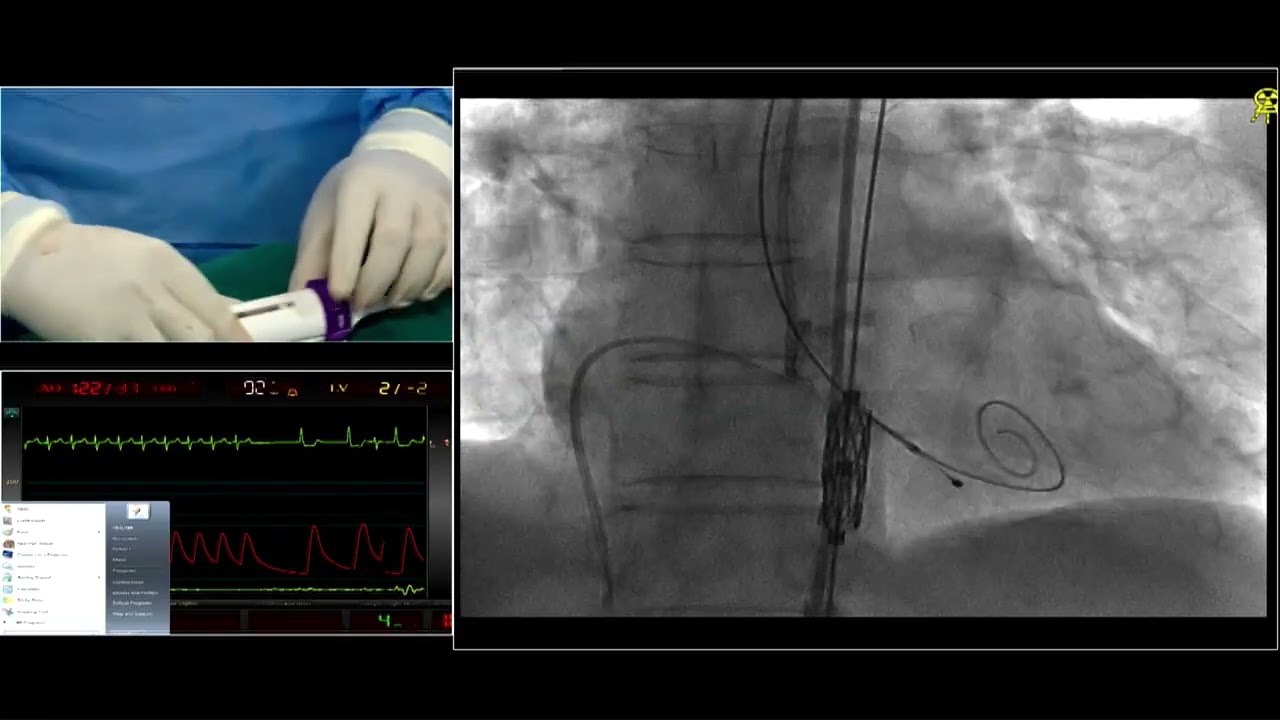

Live in box TAVR case presented at India Valves 2025 from Narayana Multi-speciality Hospital, Ahmedabad.